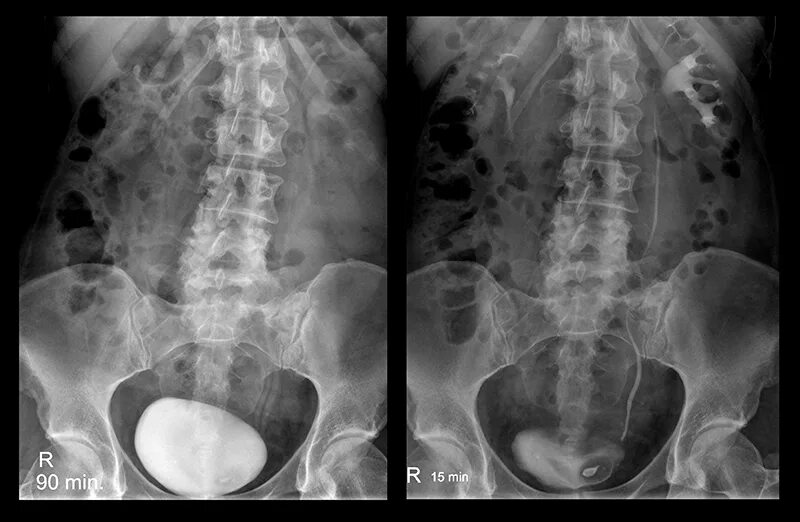

Урография с контрастом